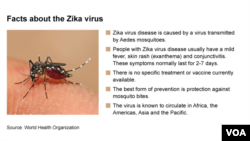

The WHO says people with the Zika virus have a mild fever, skin rash and conjunctivitis (red eye) with symptoms lasting between two to seven days. The best prevention against Zika virus, experts say, is protection against mosquito bites as no vaccine or treatment is available.